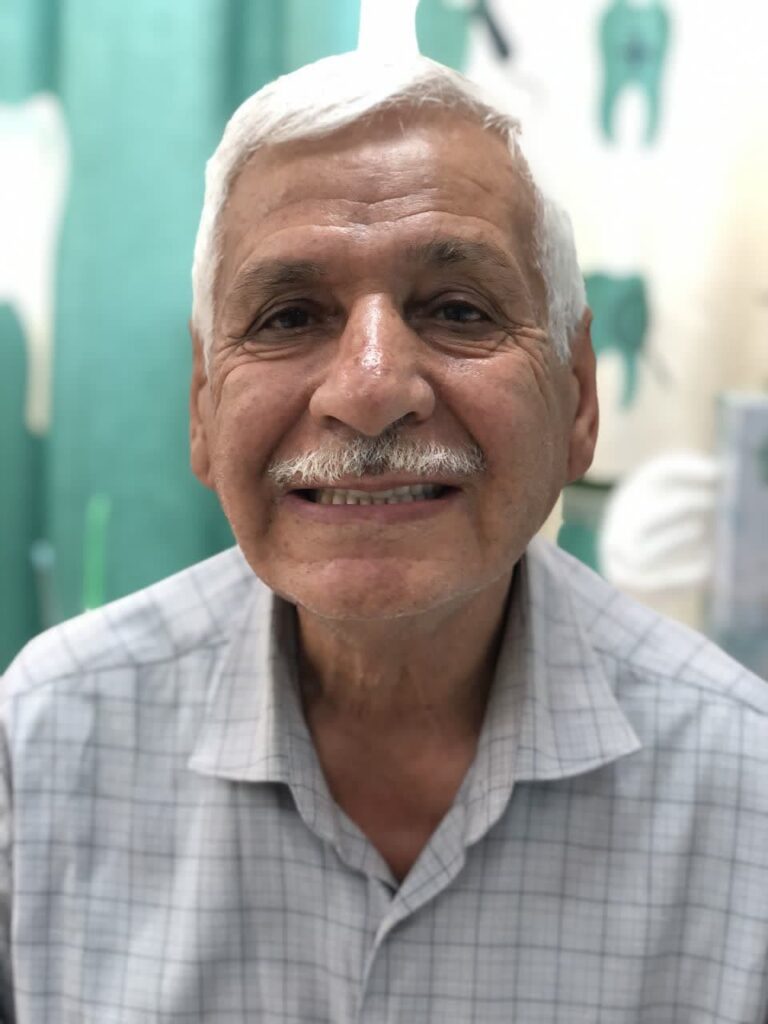

نمونه کارهای قبل و بعد از تحویل پروتز فک بالا و پایین دندان پزشکی رایان

قبل از تحویل پروتز فک بالا و پایین

بعد از تحویل پروتز فک بالا و پایین

نمونه کارهای قبل و بعد از تحویل پروتز فک بالا و پایین دندان پزشکی رایان

بعد از تحویل پروتز فک بالا و پایین

بعد از تحویل پروتز فک بالا و پایین